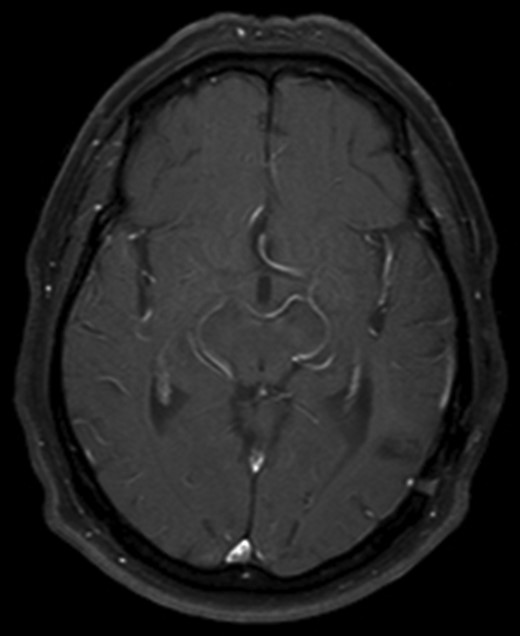

After recovering from surgery the patient had a course of whole brain radiation therapy (30 Gy). He remains well at 10 years following initial presentation, with no clinical or radiological evidence of recurrence (Fig. 3).

Axial T1 with Gadolinium MRI showing no evidence of recurrence at 10-year follow-up.